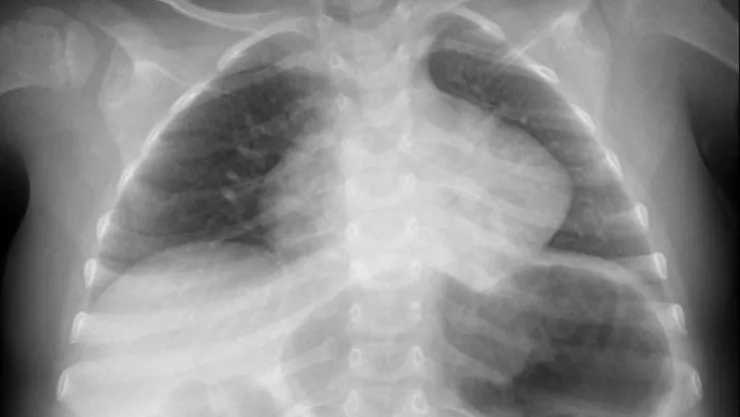

Este no es el primer caso donde un menor es internado por ingerir objetos innecesarios, pues en Bulgaría, médicos le salvaron la vida a una niña de tres años que llevaba más de un mes con una moneda en el esófago. Los padres llevaron a la menor al doctor por fiebre, sin embargo, fue una radiografía la que reveló que tenía una moneda en el esófago, pero nunca presentó dificultades para comer, tomar agua y respirar.